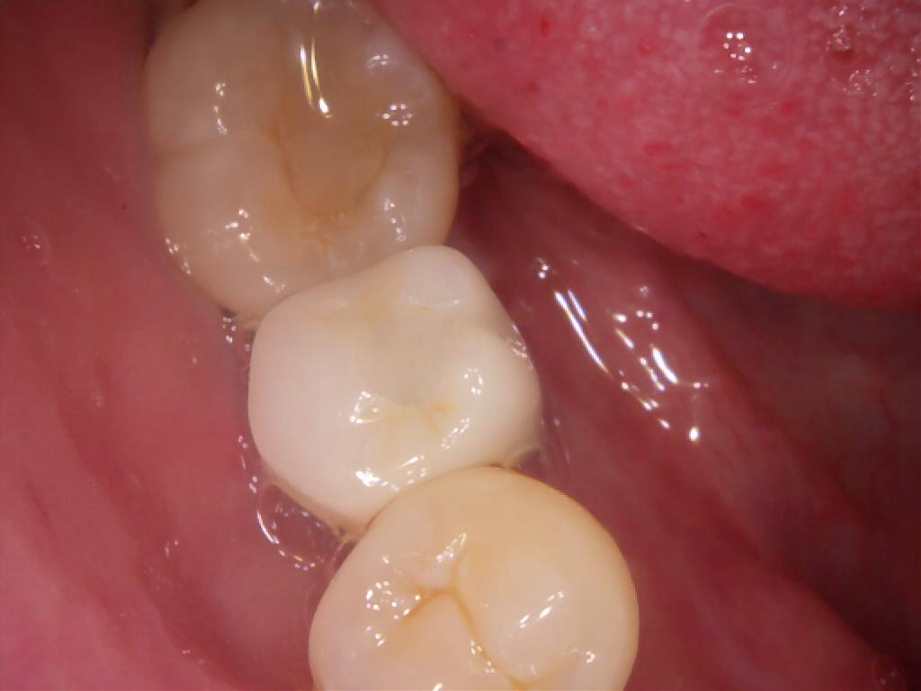

治療前

-

治療後

- 治療名称

- 右下6番欠損によるインプラント治療

- 患者の症状

- 20年前に抜歯してからそのままなのでどうにかしたい。

- 治療内容

- まず、CT撮影による精密な骨の分析・治療計画を立てガイドを使いインプラント埋入しインプラントが骨と結合するのを待つ間に仮の歯を入れます。その後本歯を作成して装着しました。

- 治療期間・回数

- インプラント埋入からジルコニアセットまで二か月半

- 費用

※自由診療となります - ■総額¥330,000(税込み) ■内訳:埋入(ガイド込み)¥200,000、仮歯¥20,000、被せ物(ジルコニア)¥80,000